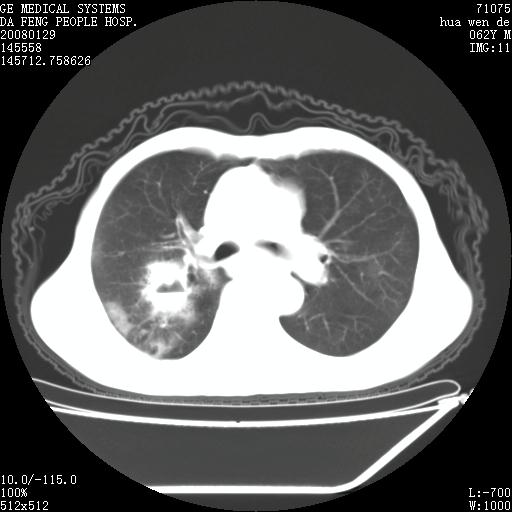

男性,67岁。作肺部检查时发现

右肺脓肿 胸腔胃

考虑1、右肺周围型肺癌可能性大。

2、贲门失迟缓症可能,建议钡餐检查。

考虑:胸腔胃并支气管瘘(并发肺炎,肺脓肿形成)。

理由:1、右上肺内病灶,空洞形成,有液平。

2、肺内多处炎症。

3、前段肺内炎症,支气管引流通畅,与肿块无关系。

1.整个食管扩张,未见明显占位性病变,贲门区亦未见明显占位病变,考虑:贲门失驰缓症;

2.右上肺病变边缘可见毛刺,囊壁厚度不均匀,周围境界较清楚,未见炎性渗出性影,右上肺外带可见片状影,边缘不清,考虑:肺癌伴空洞形成、右上肺炎。

食管全程扩张,壁均匀不厚,喷门失弛缓症

右上肺空洞可见液平,临近肺野磨玻璃密度,考虑1.结核2.脓肿